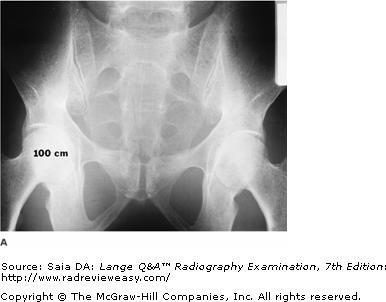

The radiograph of the pelvis shown in the figure below is unacceptable because of

C scattered radiation fog.

-Radiographic contrast, especially in analog images, can be greatly affected by changes in kilovoltage (see figures below). As kilovoltage increases, a greater number of high-energy photons are produced at the target. These photons are more penetrating, but they also produce more scattered radiation, contributing to lower radiographic contrast as a result of scattered radiation fog. Radiograph B was made using 100 kVp and 18 mAs. Radiograph A was made of the same part using 80 kVp and 75 mAs, all other factors constant. The image details in radiograph A are far more perceptible as a result of the production of less scattered radiation